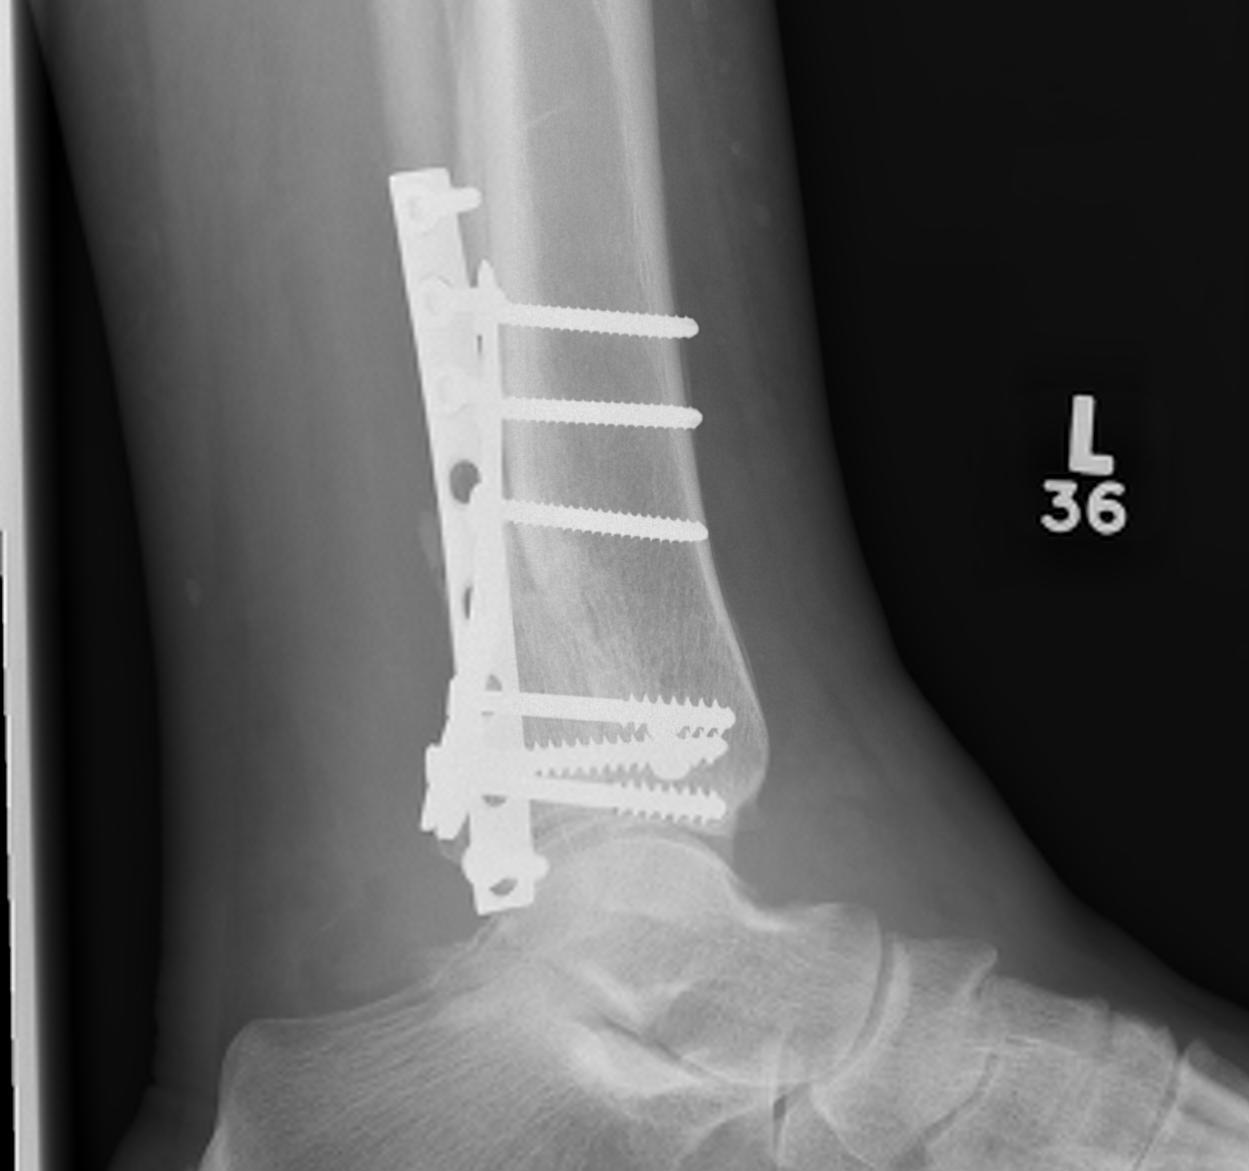

Operative Management

Diabetes / elderly / fragility fractures

Issues

High risk infection / wound complications / loss of fixation

Timing of surgery

Operate when swelling reduced / wrinkling / resolution of blisters

- risk not being able to close wounds / infection

- higher risk with bimalleolar / 2 incision operations